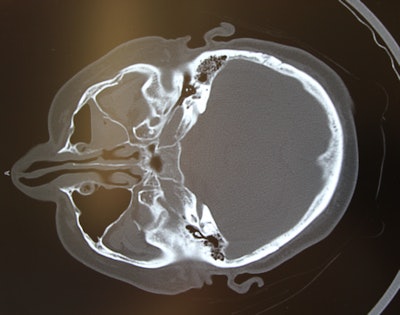

Preoperative CT scan (above) shows a left-sided zygomaticomaxillary complex fracture that is moderately displaced and rotated. After sublabial access and mobilization, reduction is confirmed with intraoperative CT (below). Reduction has been achieved and no further incisions are necessary.